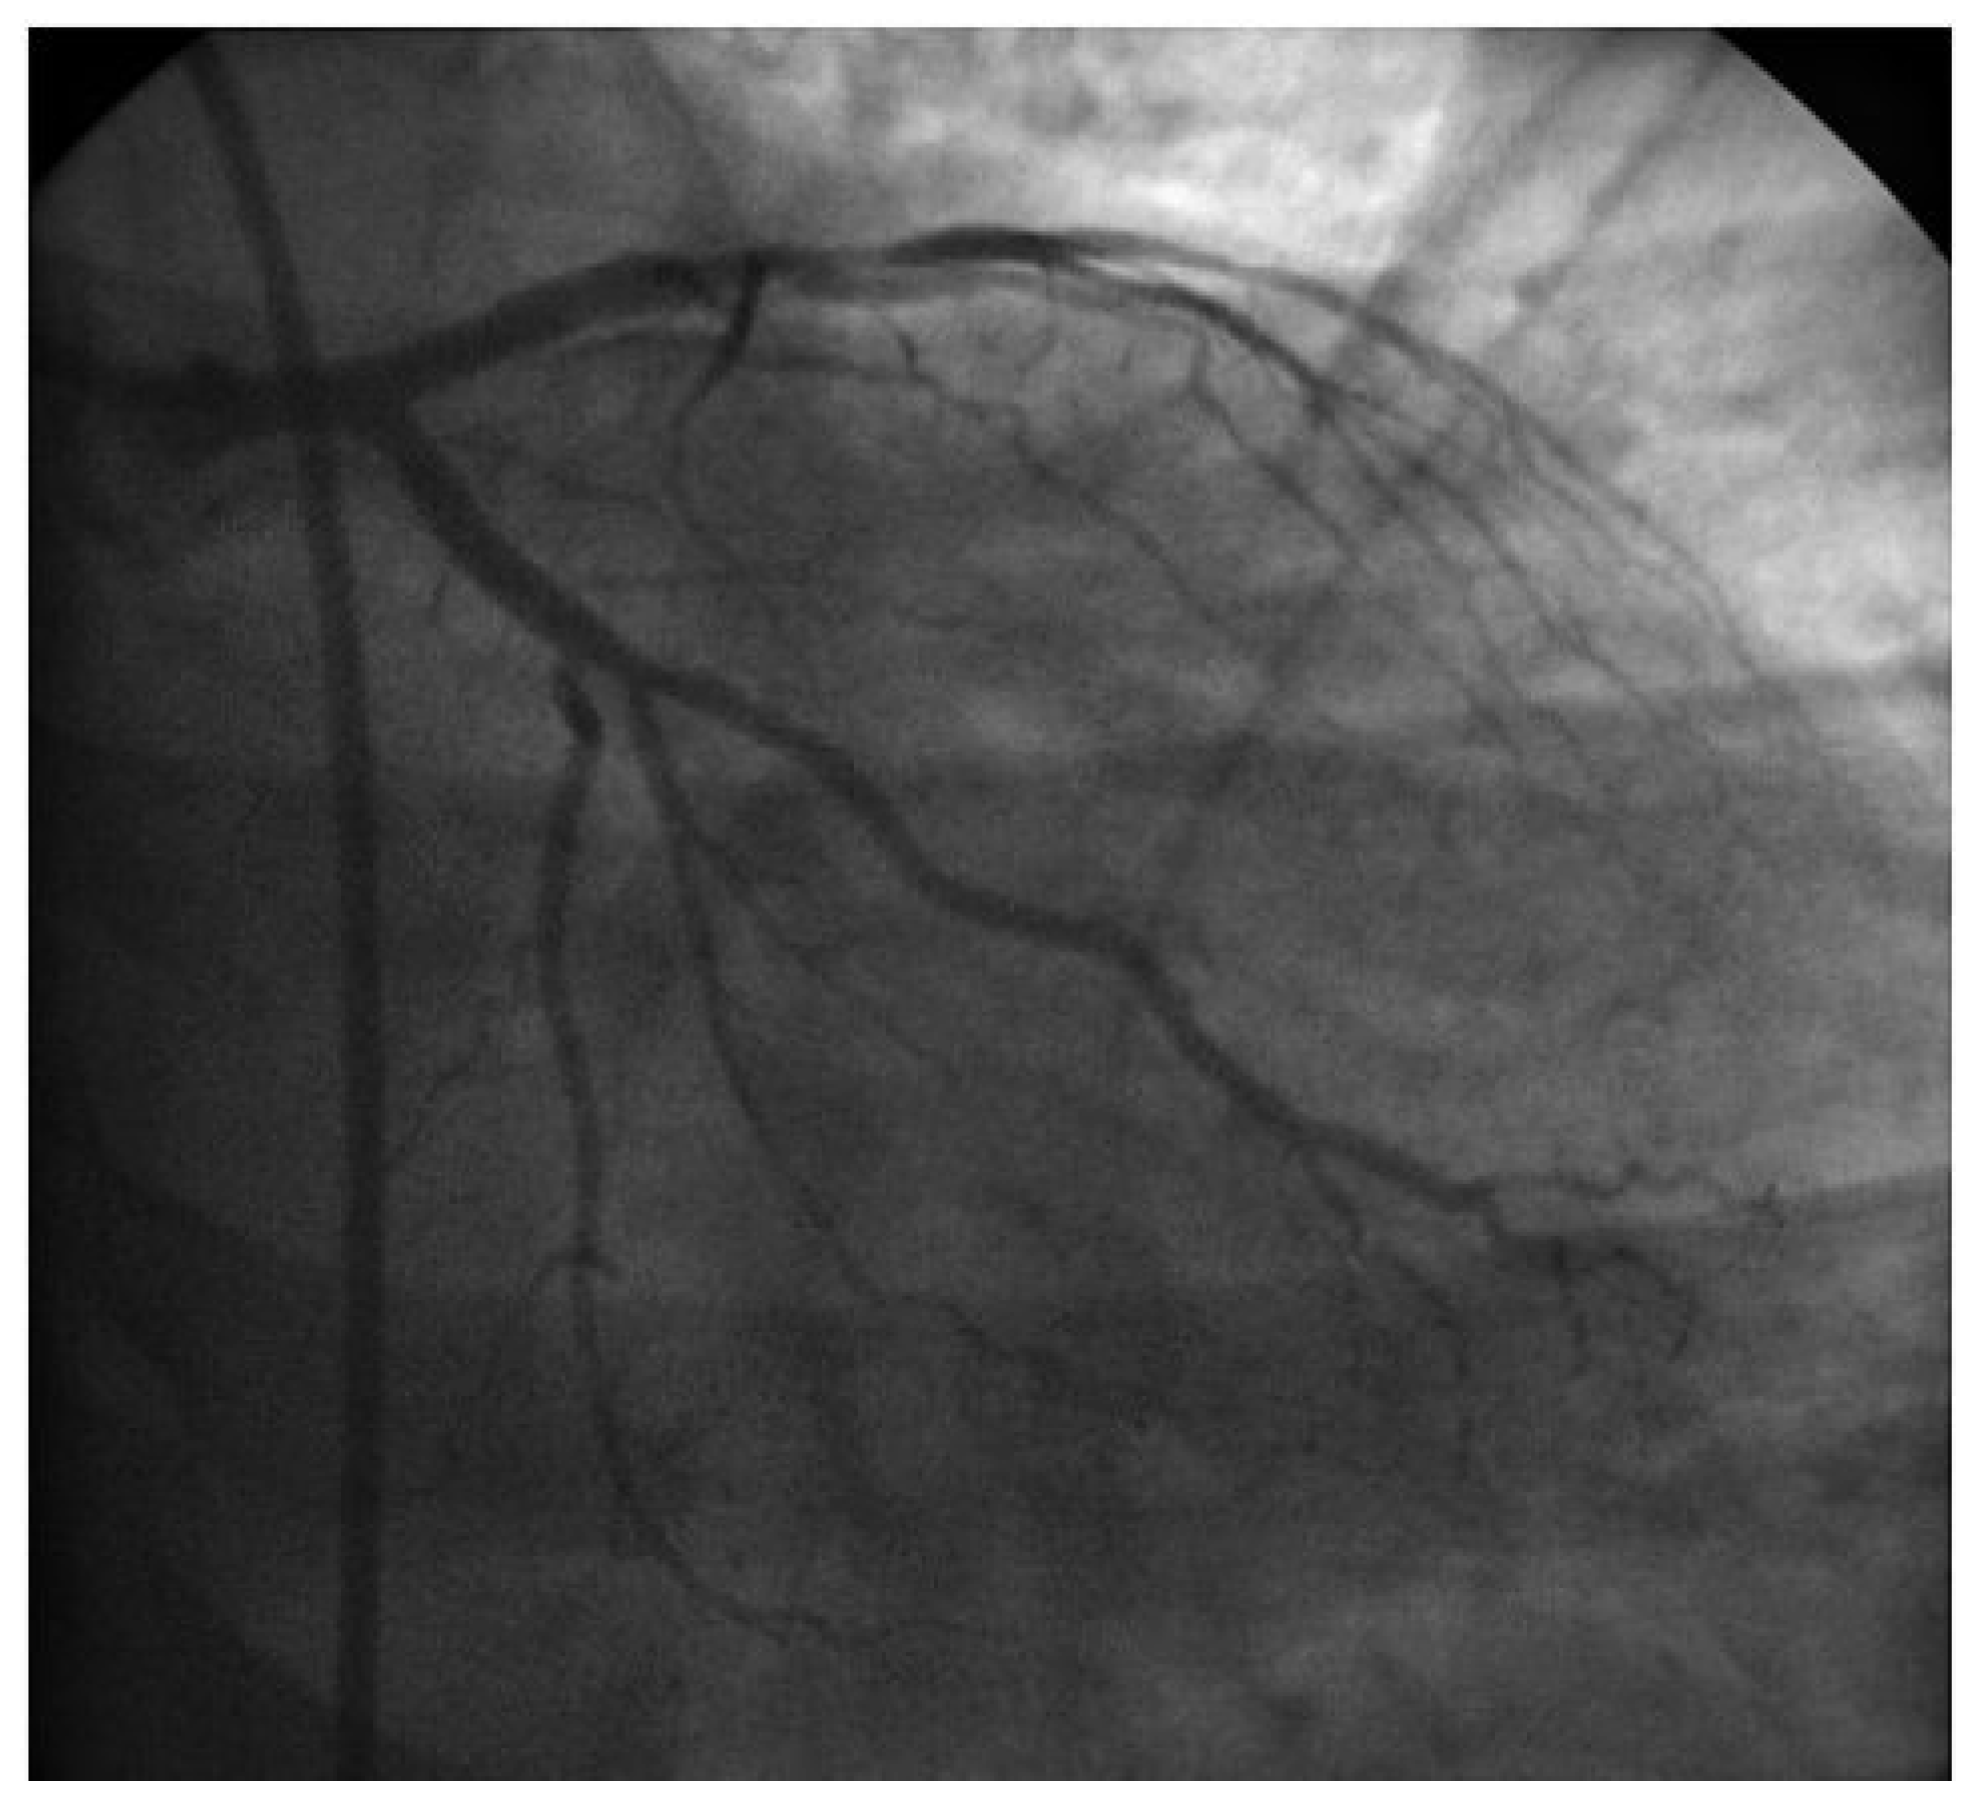

Revascularization After Removal of Broken Catheter from Left Circumflex Coronary Artery

Case report